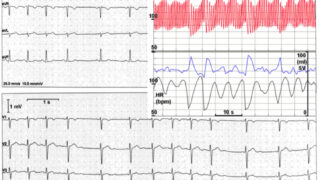

洞頻脈(Sinus tachycardia) 洞結節からの興奮が増加し、心拍数が100/分以上になった状態を洞頻脈と言います。洞結節からの刺激なので波形は洞調律の時と変わりませんが、脈は頻脈となります。 原因 洞頻脈を引...

不適切洞頻脈(inappropriate sinus tachycardia) 不適切洞頻脈は「不適切洞頻拍症候群」とも呼ばれており、心臓の洞結節が生理的な範囲を超えて不適切に興奮することで頻脈になっている状態です。若年の女性に多く...